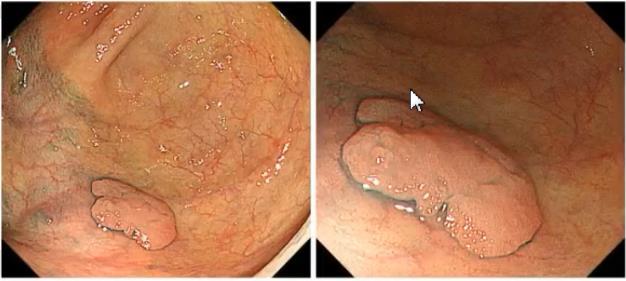

肠镜:乙状结肠距肛门20cm见1枚半球形息肉,大小约12mm×10mm,周边见白斑,表面充血,触之易出血,靛胭脂染色后观察,病变pit Vi型,用啄木鸟刀行ESD术完整剥离(2019年5月14日)。

第1步观察微血管和表面的结构,发现病变介于2A和2B之间,用色素内镜进一步评价微表面的结构,经染色后观察pit分型为鲑鱼卵样外观,管状的ⅢL型,中间夹杂着圆形的Ⅰ型,因此这个病变是ⅢL和Ⅰ型混杂,也就是ⅢL-2型。